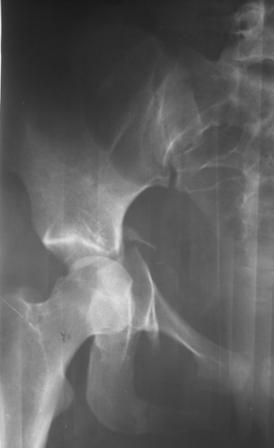

30/11/04 |  30/11/04 |  30/11/04 |  14/12/04 |  14/12/04 |  14/02/05 |  14/02/05 |  21/02/05 | Уважаемые коллеги! Случилось вторичное смещение вертлужной впадины после операции. Посоветуйте, что делать. Пациентка 18 лет. Травма 19.11.04. D.s.: Закрытыый Т-образный высокий перелом правой вертлужной впадины. Закрытый перелом м\мыщелкового возвышения левой б\берцовой кости. 9.12.04 операция - открытая репозиция, остеосинтез переломам вертлужной впадины. 30.12.05 выписаны на амбулаторное лечение с рекомендациями не вставать на правую ногу. 14.02.05 при контрольном осмотре на Р-граммах выявлено вторичное смещение передней колонны. Клинически подвывиха нет, имеется умеренная приводящая контрактура правого тазобедренного сустава, гипотрофия мышц н\конечностей. Госпитализирована в травмотделение. Выполнено КТ. Имеется смещение передней колонны кнутриЮ диастаз 8 мм. Посоветуйте пожалуйста, что предпринять в данной ситуации.